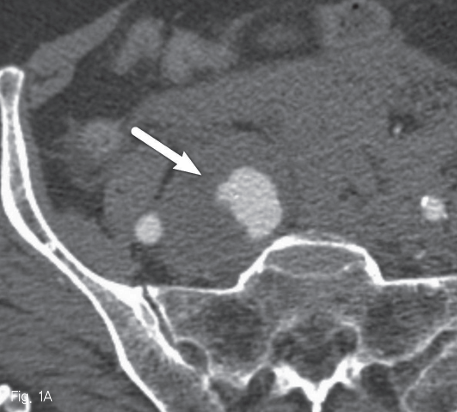

내원 당시 시행한 CT상 복부 대동맥 전체와 양측 총장골동맥 그리고 오른쪽 내장골동맥에 걸쳐 동맥류가 있으며 내부에 혈전이 동반되어 있었음. 오른쪽 내장골동맥의 직경은 최대 약 15mm로 측정되었으며 근위부에 거짓동맥류와 조영제의 혈관 외 유출이 확인됨. 또한 후복막강 혈종이 동반되었으며 이는 오른쪽 신장의 상극 주변까지 퍼져 있었음 (Fig. 1a and 1b).

Fig 1A

Axial CT image

A. shows aneurysm of right internal iliac artery(white arrow).